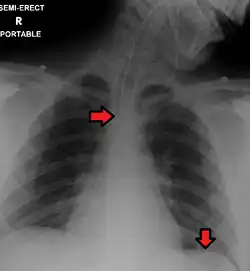

Fluid in space between the lung and the chest wall is termed a pleural effusion. There needs to be at least 75 mL of pleural fluid in order to blunt the costophrenic angle on the lateral chest radiograph and 200 mL of pleural fluid in order to blunt the costophrenic angle on the posteroanterior chest radiograph. On a lateral decubitus, amounts as small as 50ml of fluid are possible. Pleural effusions typically have a meniscus visible on an erect chest radiograph, but loculated effusions (as occur with an empyema) may have a lenticular shape (the fluid making an obtuse angle with the chest wall).

Pleural thickening may cause blunting of the costophrenic angle, but is distinguished from pleural fluid by the fact that it occurs as a linear shadow ascending vertically and clinging to the ribs.